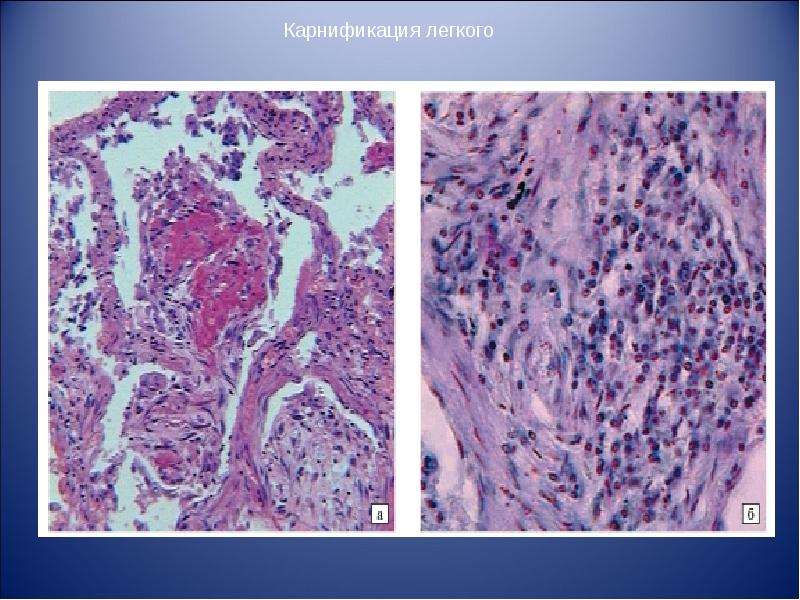

Карнификация Легкого: Микропрепараты и Диагностика

Раздел: Калейдоскоп образов